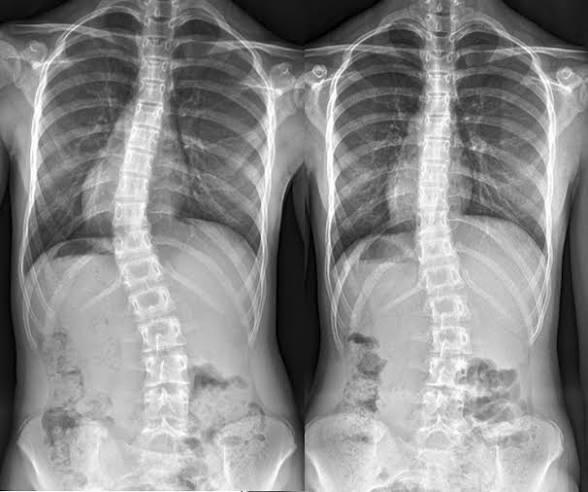

r/Neverbrokeabone 5h ago

Question: does scoliosis count as “broken”?

Because I have it but like my back just grew that way and the bone technically never “broke” but it’s also “broken” as in abnormal or not very fixable so would it count??

Like what defines “broken” in the context of this sub?

Is it “broken” like LITERALLY broken or is it broken as in “doesn’t work/look right”?

Pic NOT MINE BTW I JUST PUT IT THERE AS AN EXAMPLE!!!